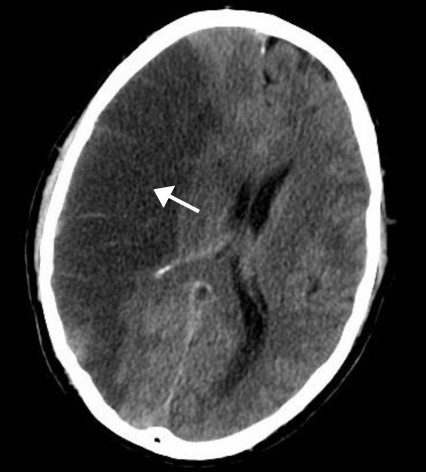

13

Q

Diagnose?

A

Intracerebral hæmoragi (ICH)